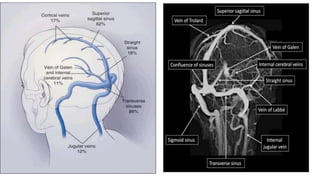

CEREBRAL VENOUS SINUS

CSF drains into Intracranial venous sinuses

CSF passively resorbrd into arachanoid granulations ,mostly withi

supiriror sagittal sinus

Incase of venous thrombosis CSF resorption decreased andvthe CSF

pressure increases

This raised ICP may ultimately give rise to papilledema